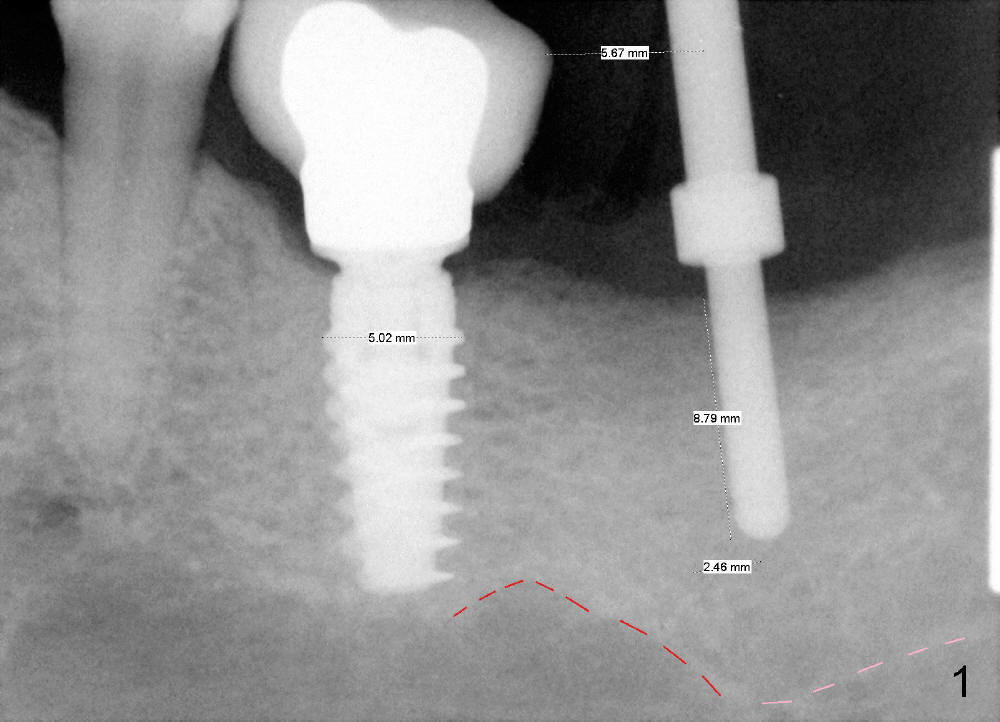

CBCT analysis reveals that there is an abnormal segment of the inferior alveolar nerve (IAN), slightly mesial to the site of #18. Intraop positional PA (Fig.1) shows that it is predictably safe to place 6.3x8 mm implant with the apical diameter (4.3 mm < 2.46 mmx2). Red dashed line indicates the abnormal segment of the IAN (pink line: normal segment). There is also some distance to IAN when 6x11 mm tap is inserted at the depth of 8 mm (Fig.2). Finally a 6.3x10 mm extra wide implant (Brushite) is placed with 3.88 mm from IAN (Fig.3).